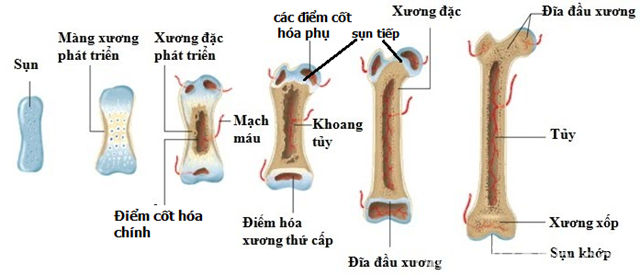

4.2. Tăng tốc quá trình tăng sinh và tái tạo tế bào xương

Các nghiên cứu tiền lâm sàng đã chỉ ra rằng các liệu pháp điện trường và điện xung có khả năng tác động giúp cơ thể điều chỉnh tổng hợp proteoglycan (PG) và collagen trong quá trình cốt hóa nội sụn, đồng thời làm tăng khả năng phát triển xương trong cơ thể sống lẫn trong ống nghiệm. Rất nhiều nghiên cứu đã được thực hiện cho thấy sự tăng tốc quá trình hình thành và chữa lành xương, đặc biệt là phẫu thuật cắt xương và cố định cột sống. [16]

Điện trường cao áp giúp cơ thể điều chỉnh tổng hợp proteoglycan (PG) và collagen trong quá trình cốt hóa nội sụn

Cho đến nay, phương pháp điện trị liệu đã được ứng dụng để nghiên cứu phản ứng của nhiều loại tế bào như tế bào gốc trung mô, tế bào xương và sụn, tế bào thần kinh và tế bào tim. Và các thí nghiệm trong ống nghiệm đã chỉ ra rằng điện trường ảnh hưởng đến các hành vi quan trọng của tế bào như bám dính, tăng sinh, biệt hóa, di cư theo hướng cũng như phân chia. [17]